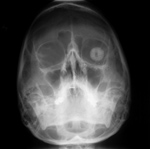

Ocular prosthesis |

Right ocular prosthesis. From Yoshino, 1994 |